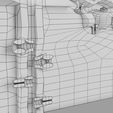

神经肌肉接头示意图

| 设计者 | deepuparmar |